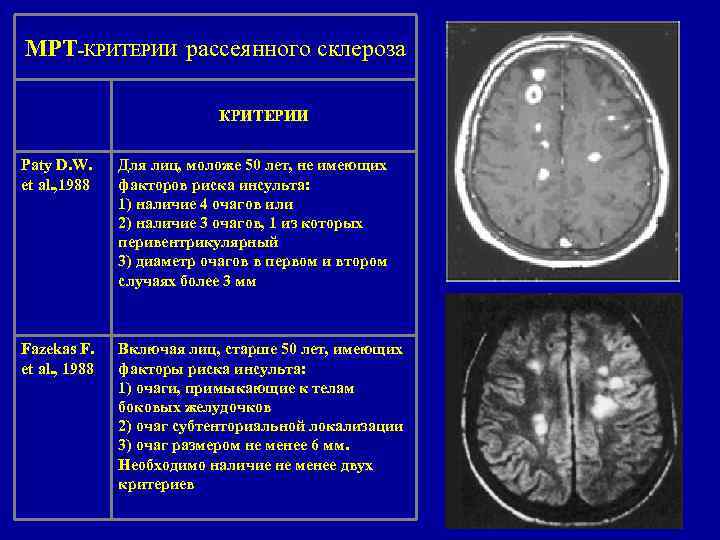

МРТ-КРИТЕРИИ рассеянного склероза КРИТЕРИИ Paty D. W. et al. , 1988 Для лиц, моложе 50 лет, не имеющих факторов риска инсульта: 1) наличие 4 очагов или 2) наличие 3 очагов, 1 из которых перивентрикулярный 3) диаметр очагов в первом и втором случаях более 3 мм Fazekas F. et al. , 1988 Включая лиц, старше 50 лет, имеющих факторы риска инсульта: 1) очаги, примыкающие к телам боковых желудочков 2) очаг субтенториальной локализации 3) очаг размером не менее 6 мм. Необходимо наличие не менее двух критериев